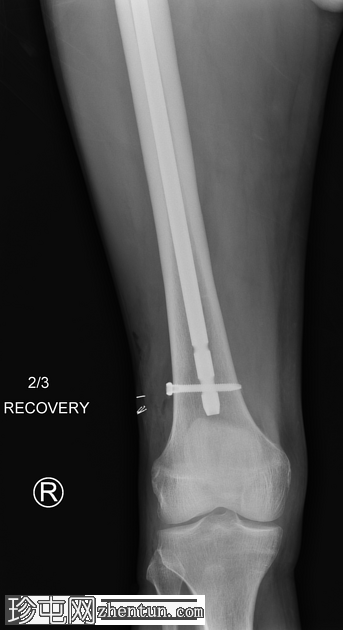

正面

术中恢复期影像学检查:股骨髓内钉固定穿过小转子水平处已知的溶骨性病变。无金属部件损坏或假体周围骨折。

患者随后接受了股骨近端置换术。

这是股骨髓内钉断裂的典型案例。由于担心股骨近端溶骨性病变以及患者存在病理性骨折的风险,因此置入了髓内钉。髓内钉断裂是一种罕见但严重的并发症。

在本例中,髓内钉断裂发生在拉力螺钉孔(穿过股骨颈的螺钉)的水平,该水平可能是髓内钉本身较薄弱的部位。靠近该水平的溶骨性病变可能导致了不稳定性和髓内钉的异常应力。